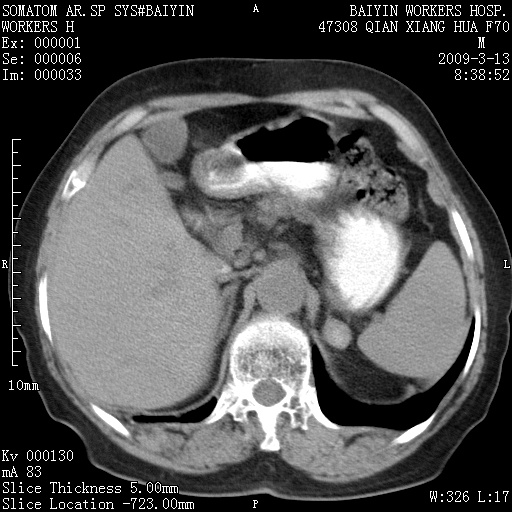

标题: CT18651:左肾上腺占位,请会诊! [打印本页]

标题: CT18651:左肾上腺占位,请会诊!

女,70岁,体检发现。

左侧肾上腺结节状软组织密度影;考虑肿瘤(肾上腺腺瘤?转移瘤?)。

左侧肾上腺占位,腺瘤?不除外转移。

左侧肾上腺占位,腺瘤可能。

左侧肾上腺占位,考虑腺瘤可能。